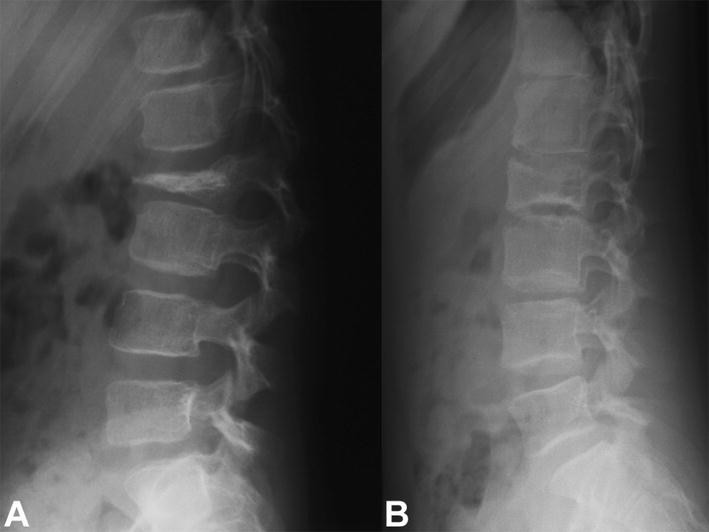

a Lateral radiograph of the lumbar spine of a 6-year-old girl with a painful osteolytic lesion of the L2 vertebral body with vertebral plana deformity. CT-guided frozen section biopsy showed eosinophilic granuloma; intralesional methylprednisolone injection was performed. b Lateral radiograph of the lumbar spine shows complete reconstitution of the lesion 7 years after diagnosis and treatment